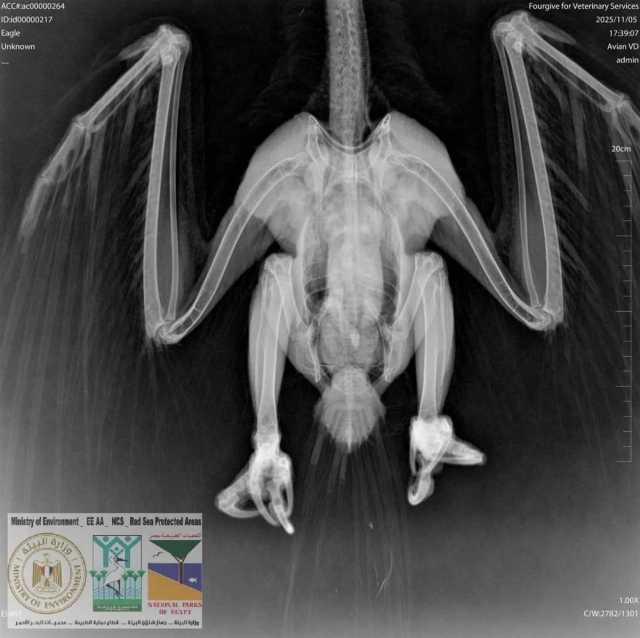

اطلاق طائر العقاب النسارى بعد علاجه بمحمية وادى الجمال

تلقت محميات البحر الأحمر بلاغًا بوجود طائر مصاب في منطقة أبو غصون – محمية وادي الجمال – حماطة جنوب محافظة البحر الأحمر، وبناءً على توجيهات وزارة البيئة، قامت محميات البحر الأحمر بتشكيل لجنة متخصصة لفحص البلاغ، وسرعة اتخاذ كافة الإجراءات والتدابير اللازمة لاستلام وعلاج الطائر، والذي تبيّن أنه من نوع العقاب النساري.

وبالتعاون مع إحدى العيادات البيطرية بمرسى علم، تم إجراء: فحوصات سريرية، وأشعة X-Ray .

وأظهرت الفحوصات عدم وجود كسور، بينما تبيّن إصابة الطائر بـ طفيليات جلدية استدعت تلقي علاجًا متخصصًا.

وخلال فترة المتابعة داخل العيادة، شهدت حالة الطائر تحسنًا ملحوظًا، وبعد استكمال العلاج والشفاء التام،

تم إطلاق العقاب النساري بنجاح في بيئته الطبيعية داخل نطاق المحمية، ليعود إلى موطنه الأصلي بأمان.